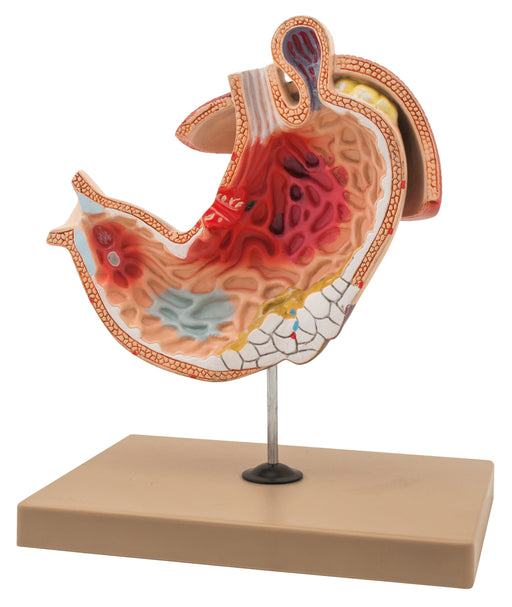

Stomach Ulcer

This 1-piece life size model describes the most common pathologies of the stomach including ulcerated gastric cancer, pyloric stenosis, gastric ulc...